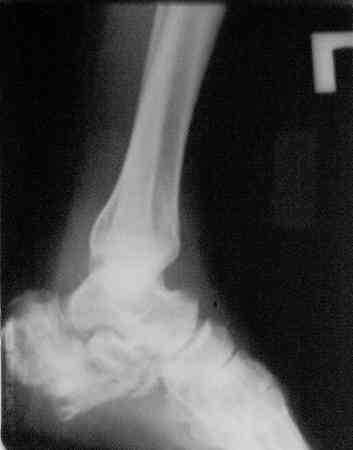

Отправляю снимки(свежие)и фото стоп.

С уважениемД.Б.

С левой стопой дело похуже. Нужен прямой снимок, да и боковой не помешает повторить на всю стопу, ну и плюс аксиальный. Готовтье аппарат.

Спасибо. Наверно, тут оптимален минимальный аппарат, позволяющий низвести бугор для восстановления формы стопы.